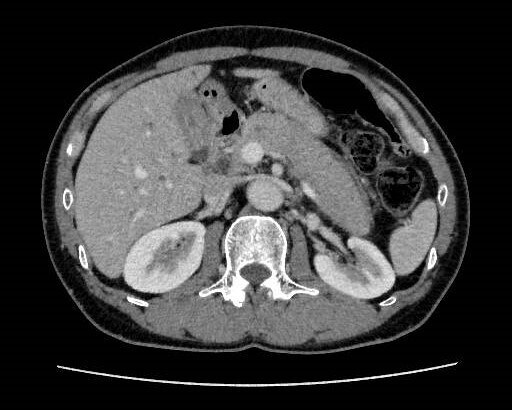

健診にて肝機能異常、皮膚黄染を認め、精査目的で当院消化器内科受診となった。今回実施されたdynamic CTではIgG4関連疾患を疑う所見が認められた。血液検査でもIgG4高値を示しており、IgG4関連硬化性胆管炎と自己免疫性膵炎が疑われ、ステロイドでの加療が開始された。

当該疾患の診断における造影CTの役割